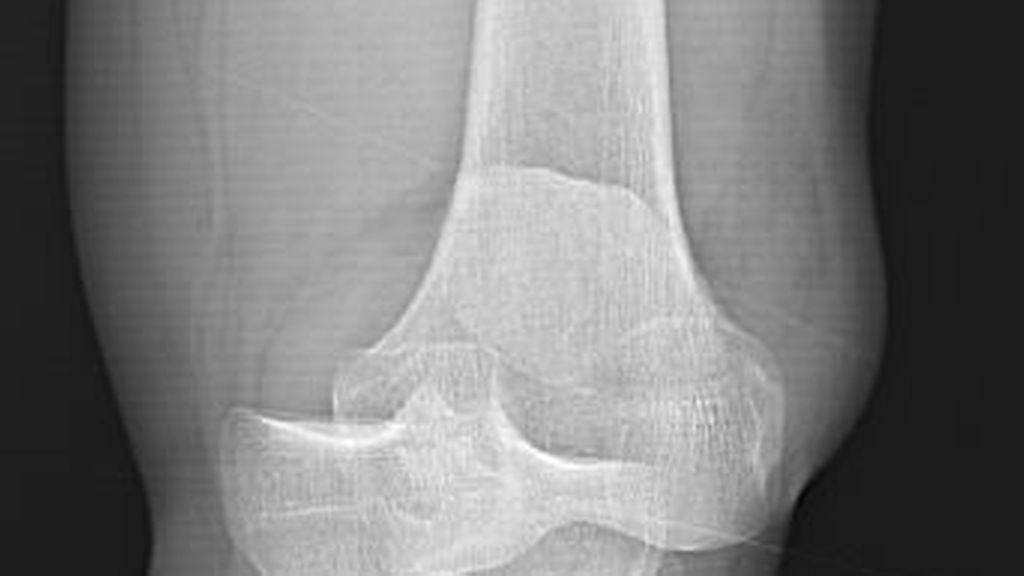

Gefäss- und Nervenverletzungen treten häufig im Zusammenhang mit einer Kniegelenkluxation auf. Henkelmann zitierte einen systematischen Review,3 der 23 Studien mit insgesamt 862 Patienten mit Kniegelenkluxationen umfasst. Bei 171 Patienten (18%) wurden Gefässverletzungen nachgewiesen. Diese kamen bei Patienten mit Schenck-Klassifikation vom Typ IIIL am häufigsten vor. Bei diesem Typ kommt es durch eine posteriore Kniegelenkluxation zur Ruptur beider Kreuzbänder und des lateralen Kollateralbandes (Abb.2 und 3). In 10 der Studien mit insgesamt 272 Patienten wurden auch Nervenverletzungen erfasst. 75 Patienten (25%) waren davon betroffen.

Abb. 2–3: Multiligamentverletzungen am jeweils linken Knie. (2) Klar ersichtlich, (3) leicht zu übersehen